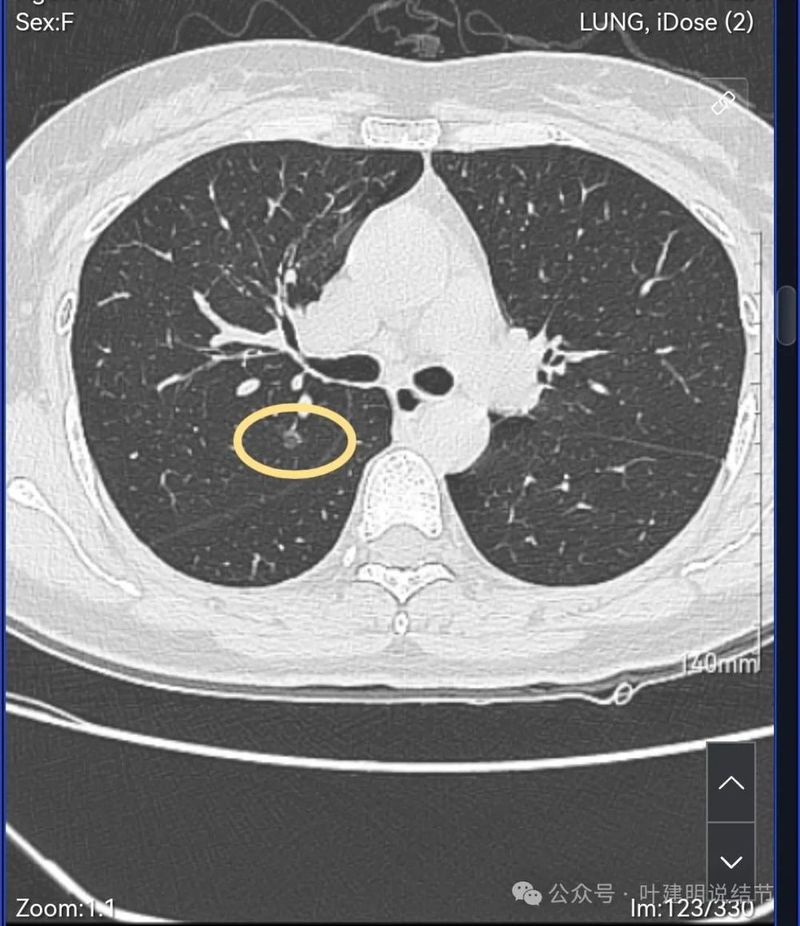

病灶2:右上叶后段磨玻璃结节,有血管征,密度不是很纯,但说不上纵隔窗可见的实性成分,整体轮廓清,瘤肺边界清楚。

右肺多发磨玻璃结节,红色的是主病灶,密度不纯,贴着叶间裂,分叶明显,考虑至少微浸润性腺癌,也可能是浸润性腺癌贴壁为主型,不能继续随访,建议手术切除,可以单孔胸腔镜下局部楔形切除。黄色的也是磨玻璃,不典型增生或者肺泡上皮增生可能性大,蓝色的肺泡上皮增生可能性大。这两处风险还低,但如果主病灶需要处理,也可以考虑同期切除。意见供参考!